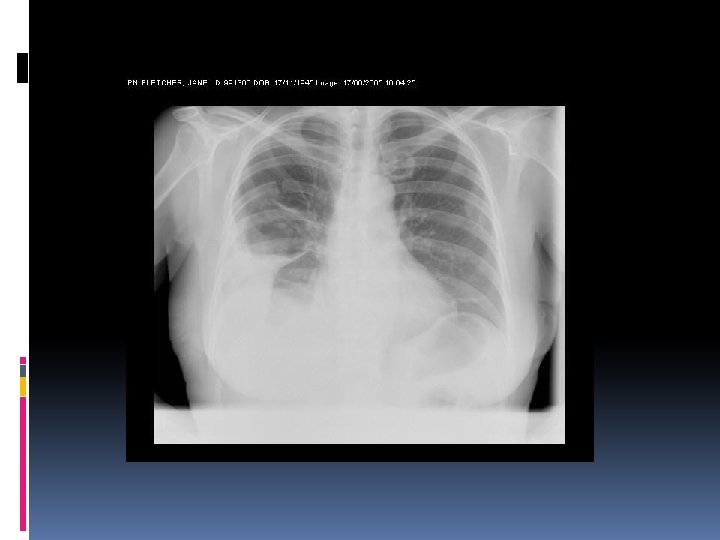

EMPIEMA PLEURICO Diagnosi Esame Radiografico del torace: mette in evidenza un’ipodiafania dell’emitorace interessato (con possibile margine laterale che si innalza fino all’ascella); possibile la presenza di livelli idroaerei per produzione di gas da parte dei batteri. In laterale può evidenziarsi, negli empiemi a sede postero-laterale, il segno tipico di un’opacità posteriore a forma di D -invertita (pregnant lady sign). Negli empiemi saccati l’ipodiafania appare come un’opacità simil-parenchimale.